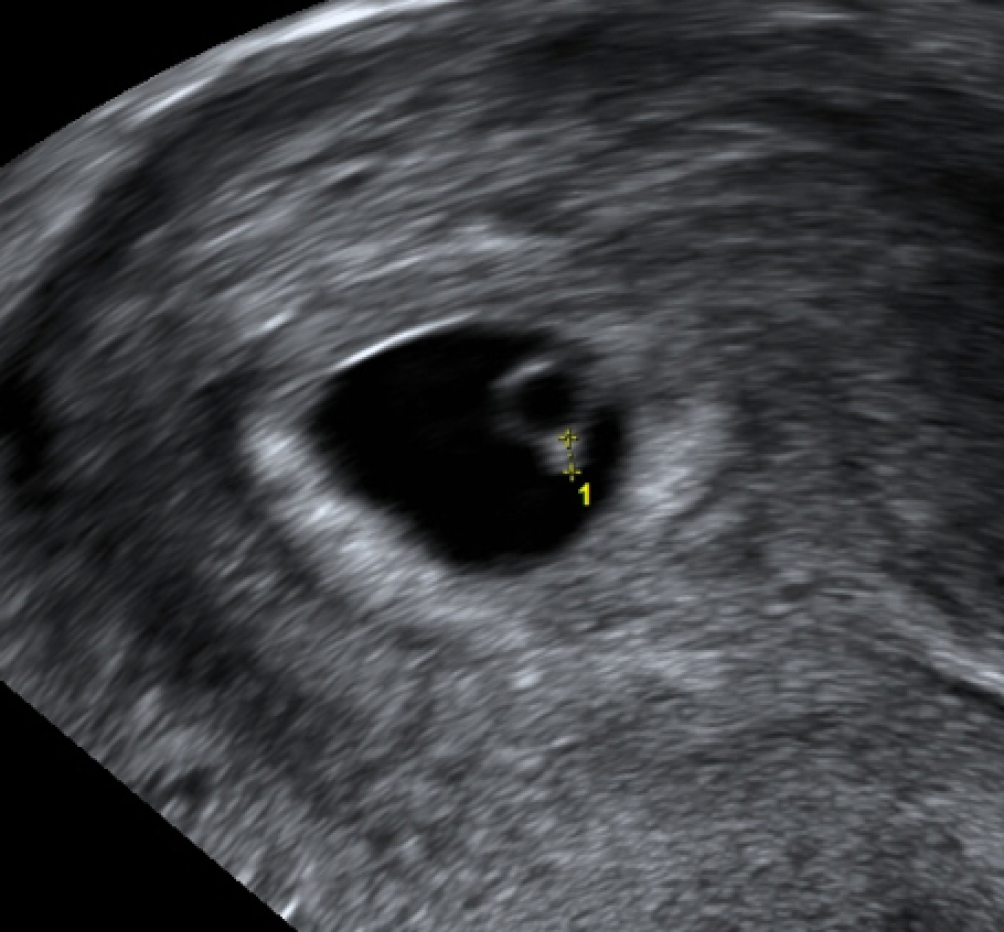

Abb. 2

Erste Zeichen eines Embryos mit 2,2 mm Länge, direkt dem Dottersack anliegend (6 + 0 SSW nach Pexsters)

Hauptfehlerquelle ist die Messung des Embryos mit dem Dottersack, hier kann durch Einbeziehung des Dottersacks in die Messstrecke das tatsächliche Gestationsalter um bis zu eine Woche überschätzt werden (Abb. 2).